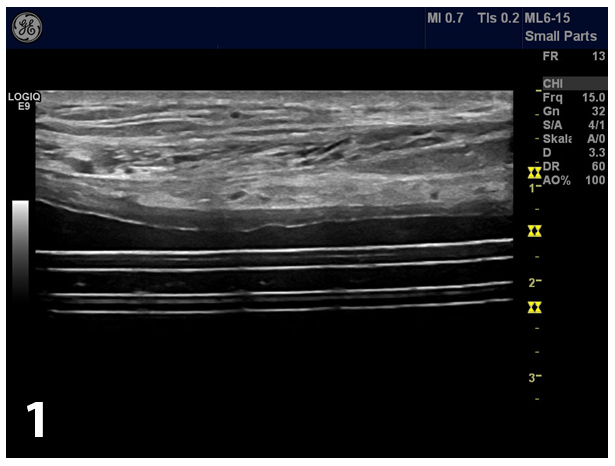

Over a period of 6 years (2007 – 2013) a 60-year old man with chronic renal insufficiency be-cause of autosomal-dominant polycystic kidney disease (APDKD) was treated by continuous ambulatory peritoneal dialysis (CAPD). In the course of his treatment he experienced 2 culture proven peritonitic events (due to taenia saginata in 2009 and staphylococcus lentus in 2012) without evidence for tunnel infection. Clinical examination revealed no fever, a soft abdomen with no pain, no tenderness or resistance on palpation. Ultrasound of the abdomen showed the intraperitoneally located catheter (Fig 1).

Ultrasound (US) is an easy way for a quick and reliable diagnosis of abdominal pseudocysts. Pseudocysts can be differentiated from ascites by their characteristic displacement of the gas containing bowel loops using ultrasound and conventional abdominal X-ray as well as by com-puted tomography. The absence of shifting dullness is also a helpful sign for diagnosis [(8)]. US is able to demonstrate the presence of localized peritoneal fluid collections as well as its size, contents and relations of the catheter to the wall. Sonographic signs include an echofree mass with or without septations. Peritoneal pseudocysts can be visualized as smooth echo-free fluid collection with pseudo-membrane. Ultrasound can also be used to percutaneously drain the pseudocysts [(4)]. Sometimes ultrasound failed to delineate the cyst due to its large size, favouring the diagnosis of ascites secondary to sclerotic peritonitis.